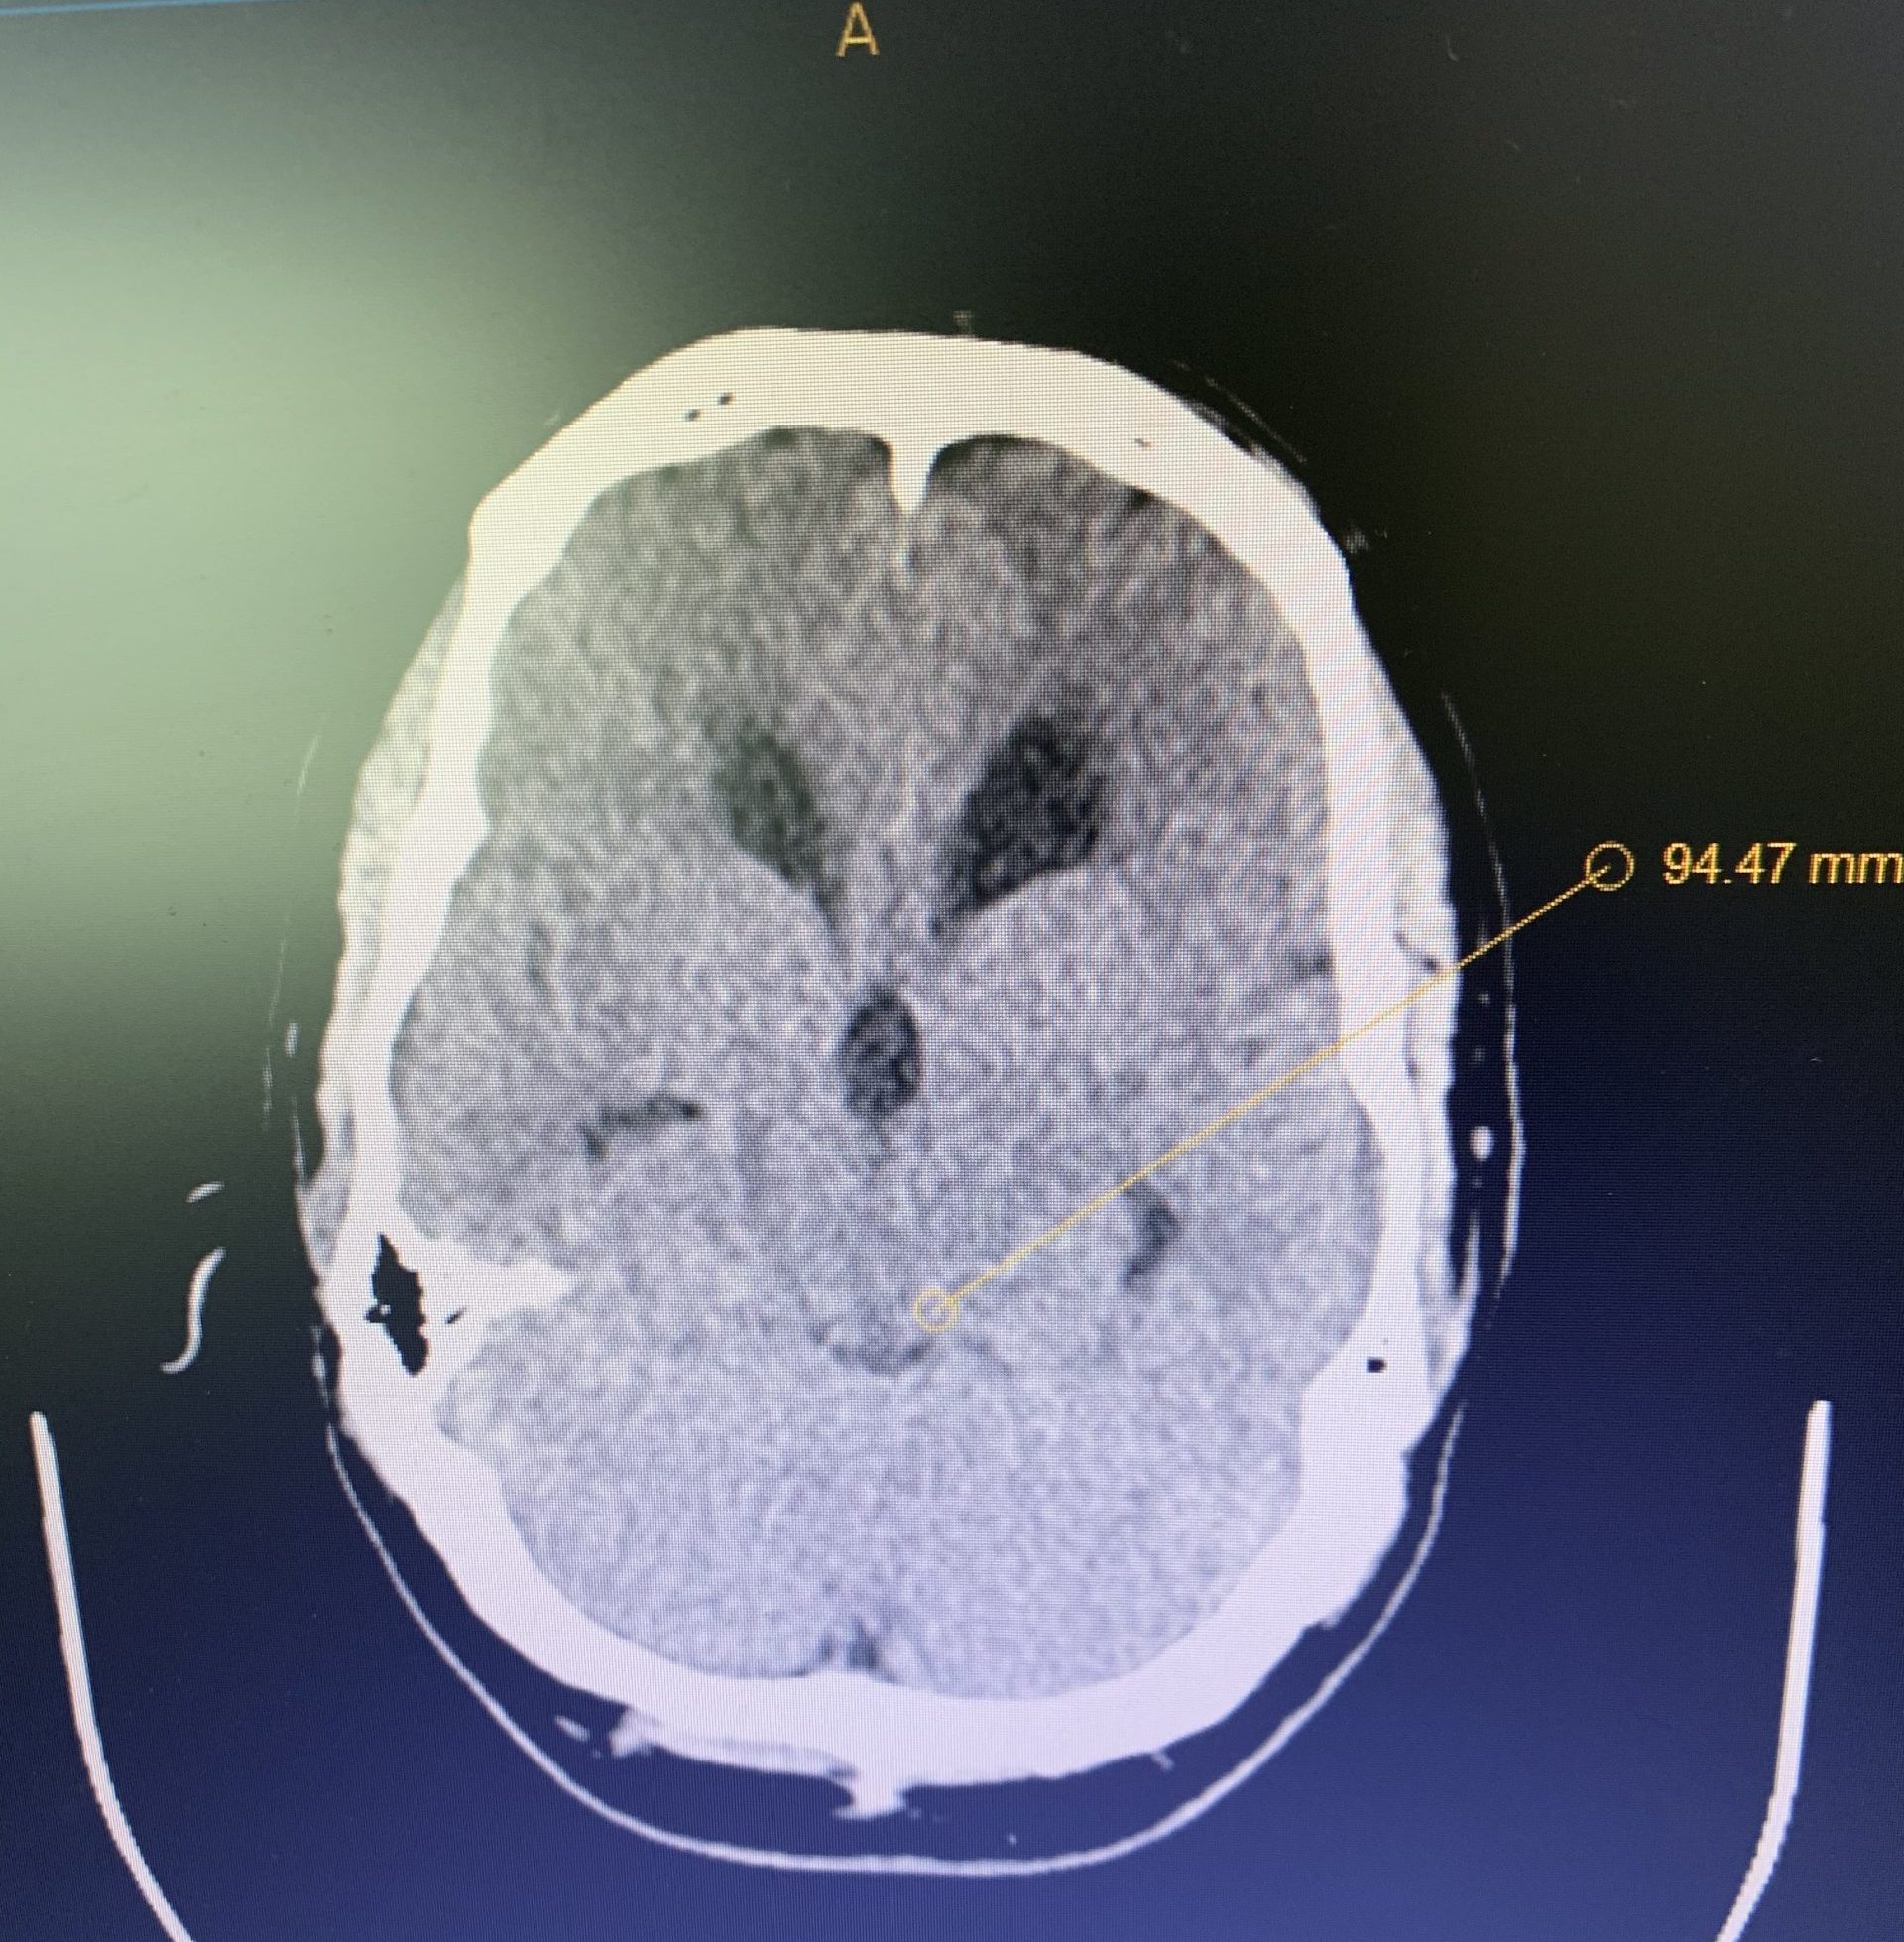

This is a 42-year-old otherwise healthy male who presented electively with progressively worsening neck pain radiating down the left arm, with paresthesia first three digits. He had a previous C6-7 anterior cervical discectomy and fusion (ACDF) two years prior, for which he recovered well. He was referred to Dr. Xavier Gaudin for a neurosurgical spine evaluation. An MRI cervical spine was obtained, which demonstrated C5-6 adjacent segment degenerative disease with a large disc extrusion resulting in severe left lateral recess and foraminal stenosis (Figure 1).

Figure 1: Preoperative MRI demonstrating C5-6 disc herniation with stenosis, adjacent to the previous C6-7 ACDF.